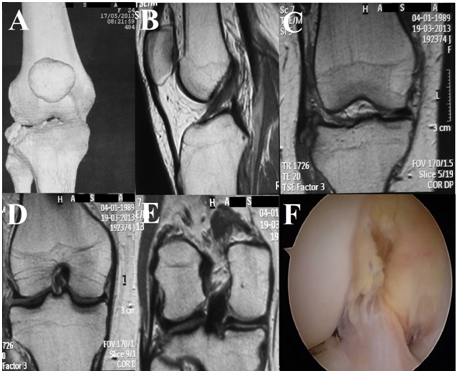

Figure 2 A: CT with 3D reconstruction demonstrating the Segond fracture; B: Sagittal MRI showing an intact ACL; C: Ccoronal MRI showing the Segond fracture; D: Coronal MRI showing an intact MCL; E: Coronal MRI showing an intact posterolateral corner; F: Arthroscopic view showing an intact ACL.

The authors opted for surgical treatment due to frequent instability complaints and the presence of the Segond fracture. In addition, the patient had not improved after three months of conservative treatment involving muscle strengthening and proprioception at the physiotherapy. Physical examination after anesthesia was not different from the one obtained before it. An arthroscopy inspection was performed confirming ACL integrity and no intra-articular lesion (Figure 2F). A 12cm curvilinear lateral approach was performed to address the Segond fracture. It started 3cm proximal to the femoral lateral epicondyle and extended distally halfway between the Gerdy’s tubercle and the fibular head around 3cm distal to the joint line. The bone fragment was considered inappropriate for fixation. It was thin and small, and the lateral structures attached to it, the ALL and/or the anterolateral capsule, were irreversibly proximally retracted impairing its anatomical fixation. The bone fragment was resected and an extra-articular reconstruction was performed with the iliotibial band (ITB) preserving its tibial insertion on Gerdy's tubercle similar to the technique described by Claes15 in 2013. However, an interference screw was used for femoral fixation.

A 10mm x 15cm strip of the ITB was prepared maintaining its distal attachment at the Gerdy’s tubercle. Its free end was prepared with Krakow sutures using Ethibond 2 (Ethicon, Somerville, NJ, USA). For the femoral fixation, an 8mm diameter tunnel was drilled at the most isometric femoral point described by Kurosawa et al.16 for ACL extra-articular reconstruction. The graft was routed deeply to the lateral collateral ligament (LCL) according to the Cooker-Arnold technique.16 An interference screw BIORCI HA 8mm x 35mm (Smith & Nephew, Inc, Andover, MA, USA) was used to fix the graft with the knee at 45º of flexion in neutral rotational. During the stability evaluation tests, it was noticed a graft rupture at the femoral tunnel aperture. The femoral interference screw was retrieved and the remaining graft at the tunnel was removed. The hamstrings were harvested. A 7mm quadruple semi-tendinosis and gracilis graft was prepared. An Endobutton CL Ultra (Smith & Nephew, Inc, Andover, MA, USA) was used for tibial fixation at the site of the avulsion. The graft was routed deeply to the LCL. It was fixed at the femur using the previous tunnel and the retrieved interference screw with the knee at 45º of flexion in neutral rotational. The ITB strip previously removed was sutured to the hamstrings graft. Final stability evaluation tests showed negative pivot-shift, negative Lachman and negative anterior drawer test. At two years follow-up, the patient presented no giving-away episodes and a good Lysholm score of 82 points (Figure 3).

Figure 3 A: Anterolateral ligament reconstructed deeper collateral lateral ligament; B: Site of tibial fixation of the graft; C: Site of femoral fixation of the graft.